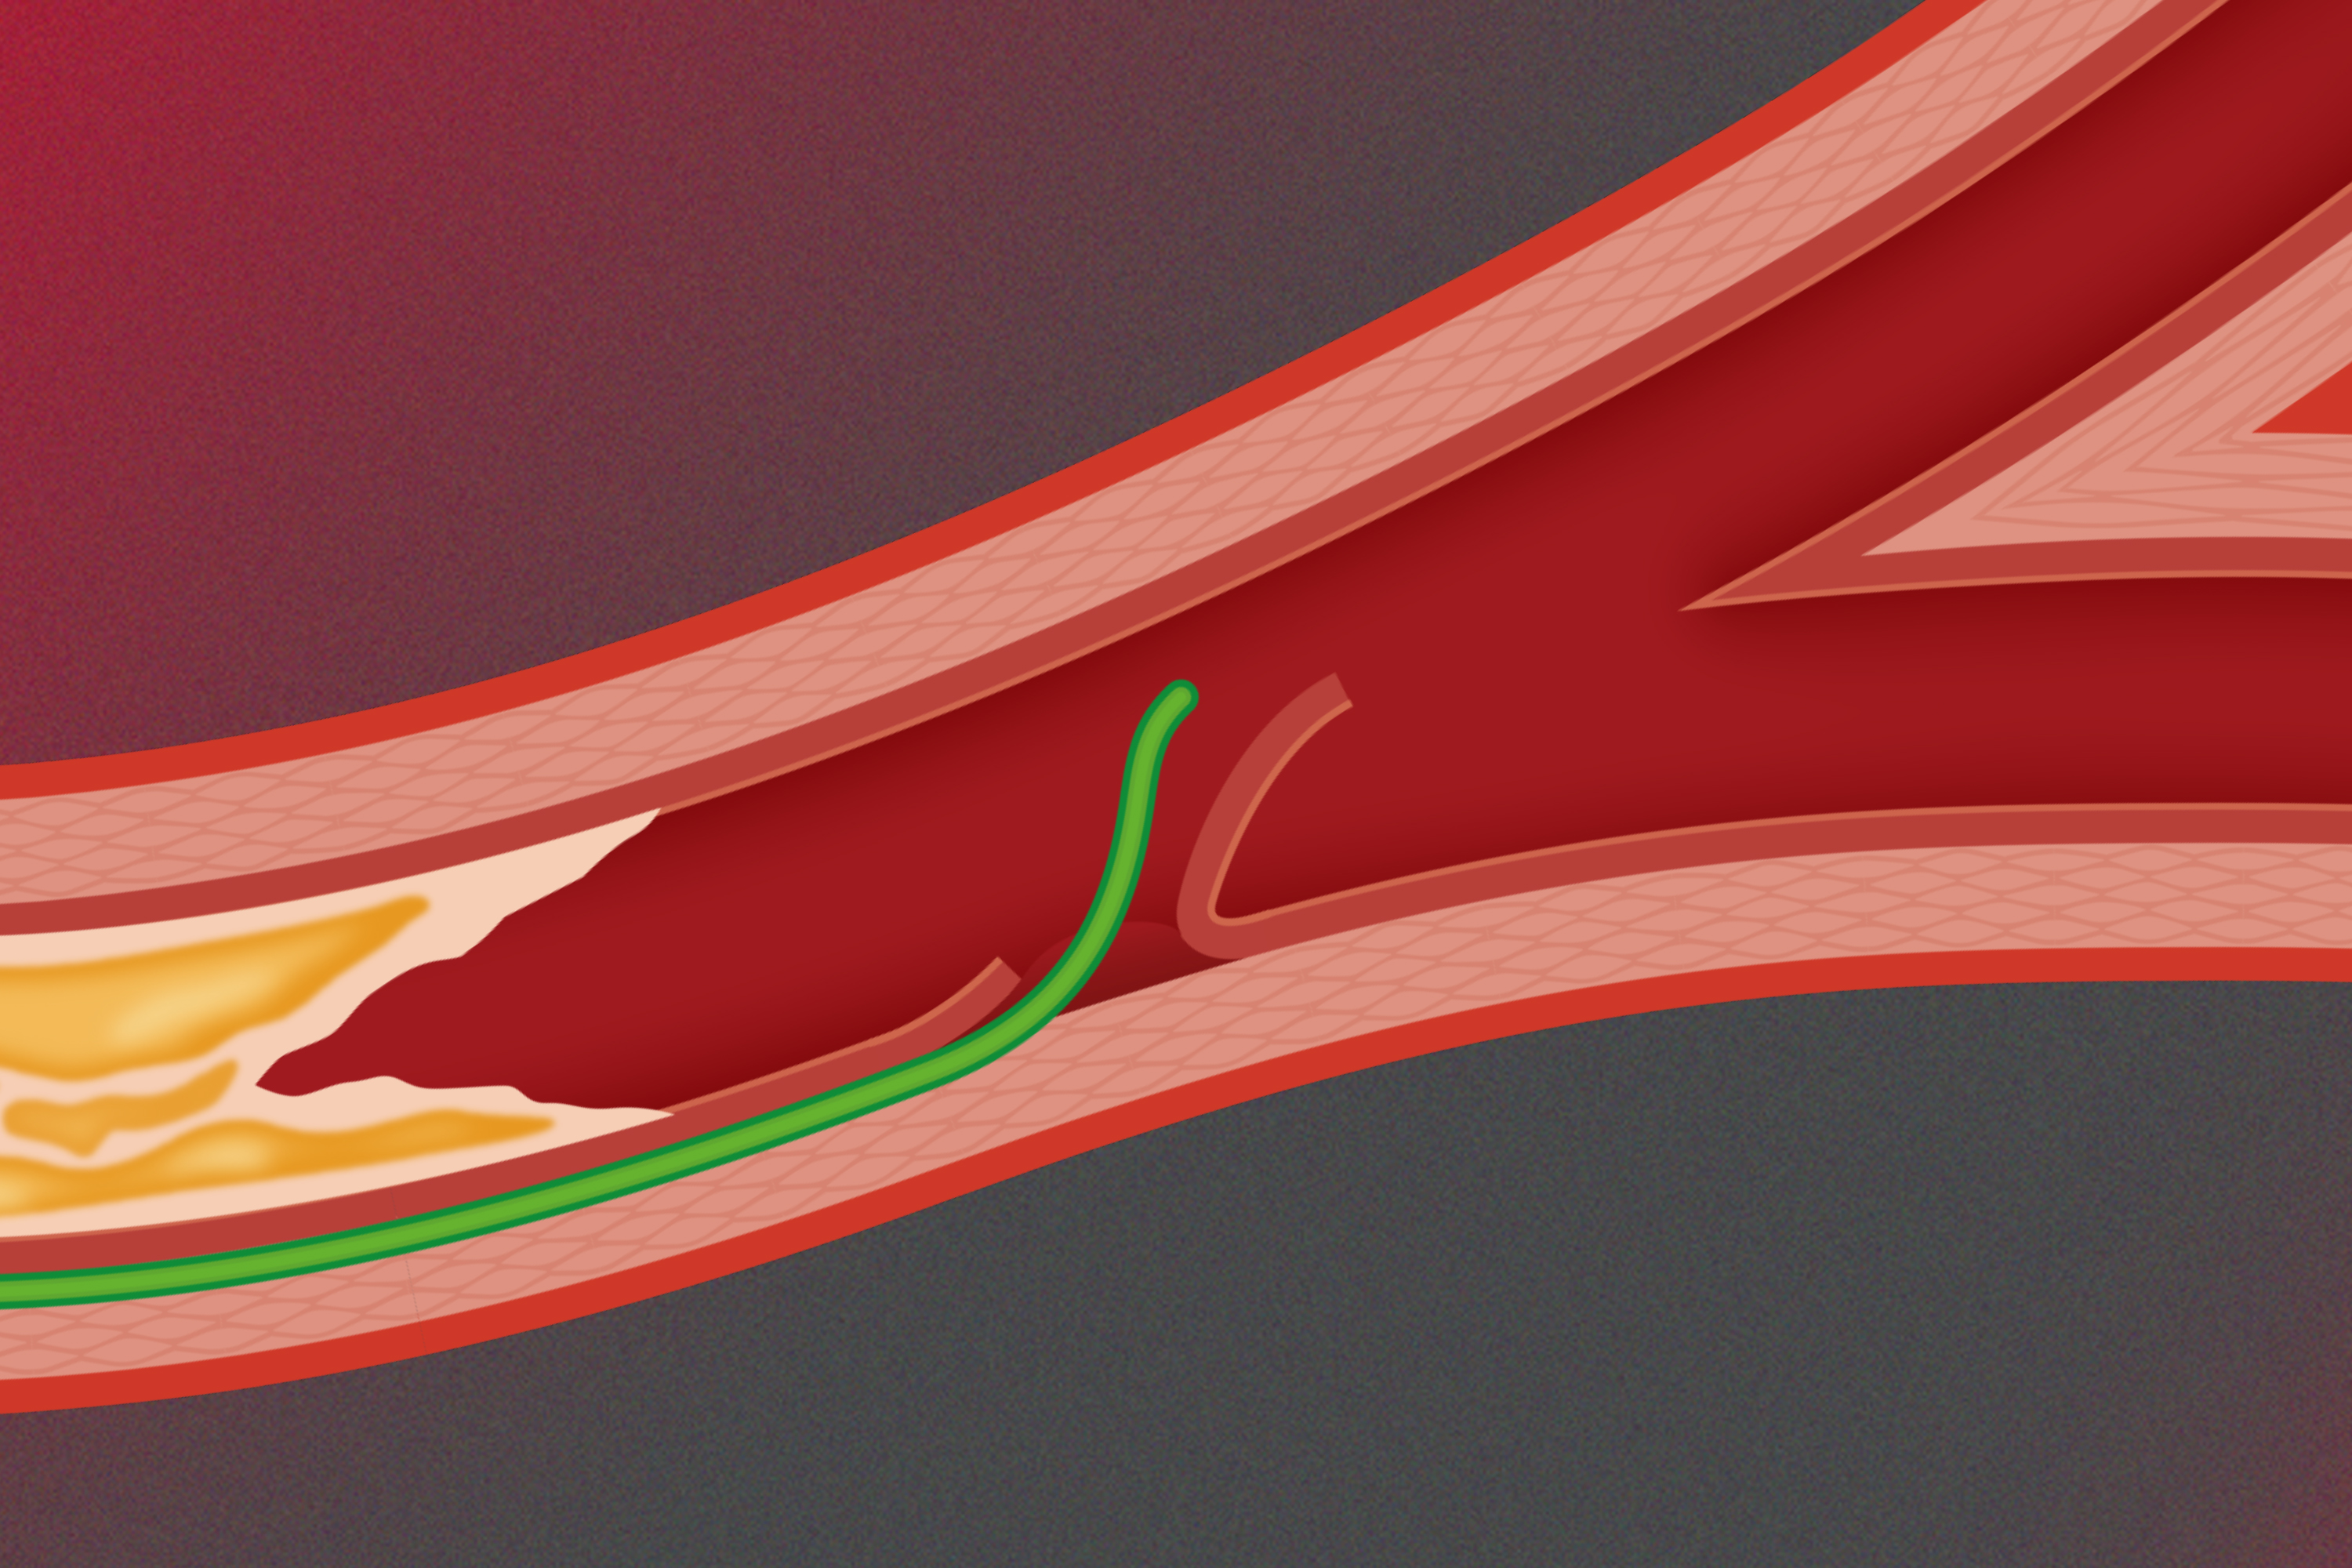

The CTO Training Pathway 2021

The CTO Training Pathway - Taking the steps to CTO mastery